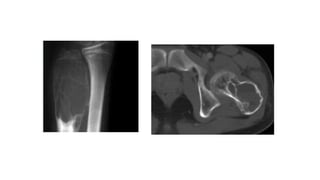

• Extremities – Involves metaphysis or diaphysis ; expansile lytic lesion

with size > 2 cm and thin peripheral cortical rim